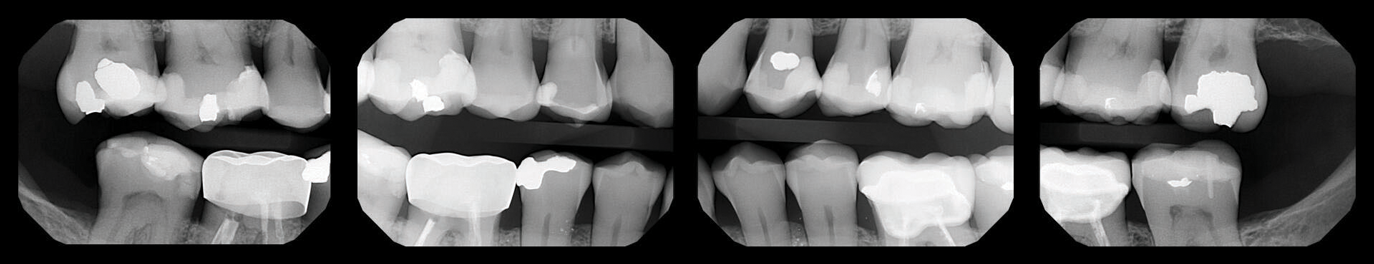

Fig 1. Case 1. Preoperative periapical radiograph showing periapical pathology associated with tooth No. 13.

Figure 1

Fig 2. Preoperative CBCT. Note periapical pathology associated with tooth No. 13 communicating with the adjacent maxillary sinus along with associated mucositis.

Figure 2

Fig 3. Immediate postoperative periapical radiograph.

Figure 3

Fig 4. One-year recall CBCT. Note resolution of prior periapical pathology on tooth No. 13, sinus communication, and MSEO.

Figure 4